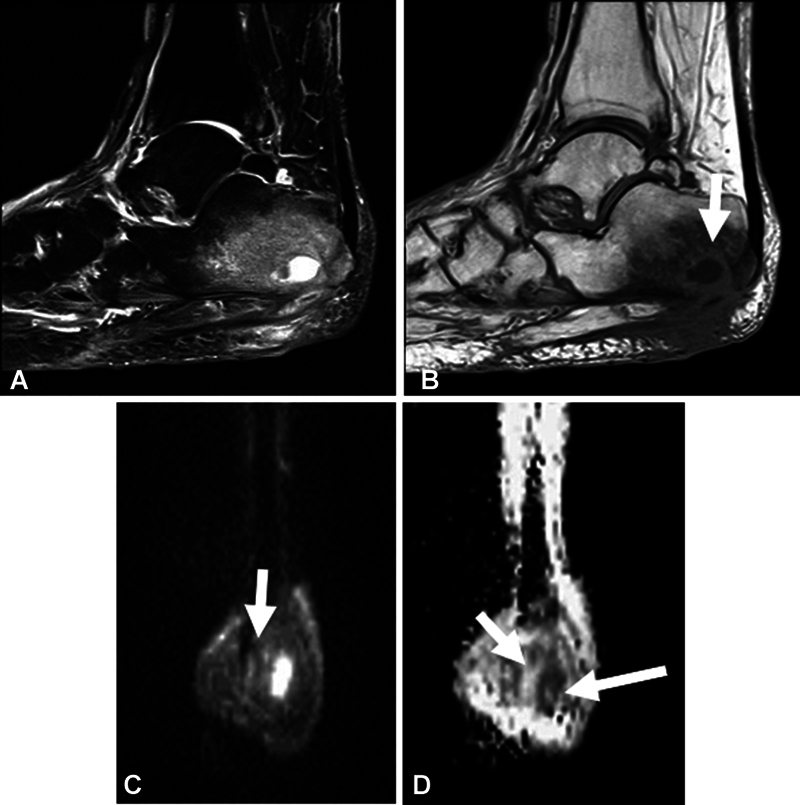

Objective  The aim of this study was to determine the sensitivity and specificity and inter-reader reliability of previously known "ghost sign" and "penumbra sign" on T1-weighted (T1W) imaging and "ghost sign" on apparent diffusion coefficient (ADC) map in osteomyelitis (OM) of the extremities. Materials and Methods  In this cross-sectional retrospective study, two fellowship-trained musculoskeletal readers blinded to final diagnosis of OM versus no OM were asked to report the penumbra sign and ghost sign on T1W images and ghost sign on ADC map, as well as diagnosis of OM. Cohen's kappa was used. Diagnostic performance measures including sensitivity, specificity, and accuracy were calculated. Results  A sample of 178 magnetic resonance imaging (MRI) scans of pathology-proven cases were included in this study, with 41 being positive for OM and 137 being negative for OM. There was a fair inter-reader agreement for imaging signs, and moderate agreement of 0.60 for OM. The sensitivities of the penumbra sign on T1W imaging, ghost sign on T1W imaging, and ghost sign on ADC map for OM are 3.7, 9.8, and 19.5%, respectively, while their respective specificities are 98.9, 97.8, and 94.5%, respectively. All three imaging signs showed a similar (good) accuracy of 76 to 78%. Conclusion  The ghost sign on ADC can be used as an additional marker for OM and is a similarly highly specific but a more sensitive sign for OM than the conventionally used penumbra sign and ghost sign on T1W imaging. Key Points The ghost sign on ADC can be used as a helpful indicator of osteomyelitis.Across two fellowship-trained musculoskeletal readers, there was a fair inter-reader agreement for imaging signs and moderate agreement for OM.The ghost sign on ADC is a similarly highly specific but a more sensitive sign for osteomyelitis than the conventionally used penumbra sign and ghost sign on T1W imaging. All three imaging signs showed a similar (good) accuracy of 76 to 78%.

Abstract Image